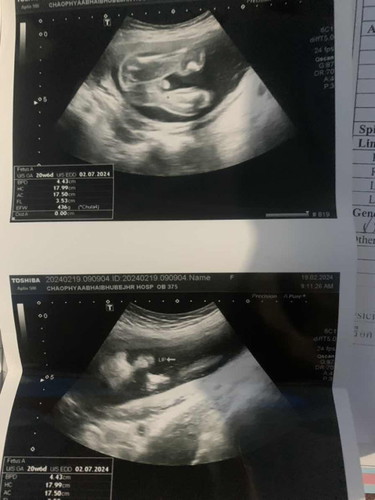

รบกวนแม่ๆช่วยดูทีค่ะน้องเพศอะไรแล้วน้องได้มีปากแหว่งเพดานโหว่ไหมค่ะ30วีค

ภาพนี้ไม่สามารถดูปากแหว่งเพดานโหว่ได้ค่ะ เพศน้องน่าจะเพศชายค่ะแม่

เดาว่าชายนะคะ